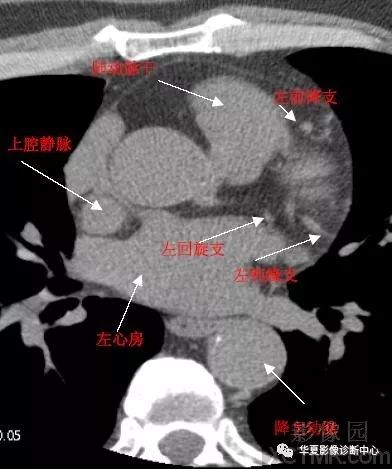

带你全面了解心脏冠状动脉ct解剖

主动脉根部层面ct和mri断层解剖

影像解剖|心脏冠状动脉ct解剖中文详细标注(图文)

所属相册:心脏冠状动脉ct解剖中文详细标注(图文 cardiac a所属相册

超全总结心脏ct解剖图谱